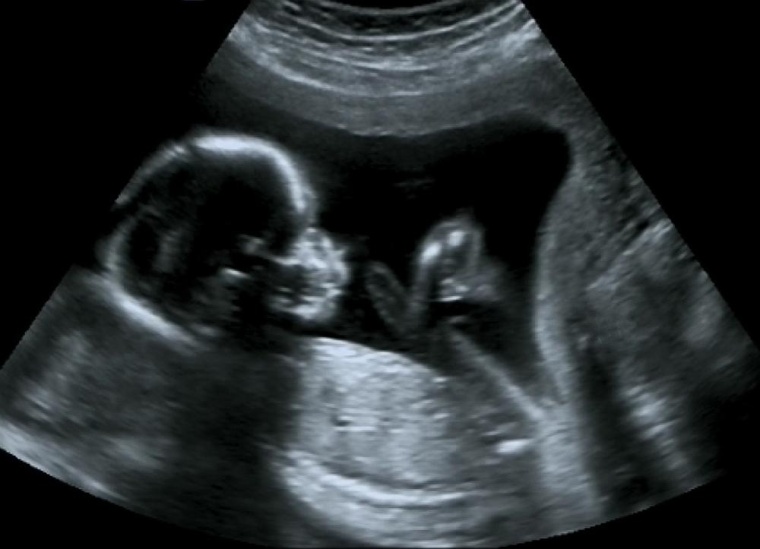

Jedes Jahr kommen in Deutschland Tausende Babys viele Wochen zu früh auf die Welt und müssen sich oft monatelang ins Leben kämpfen. Je früher die Babys geboren sind, desto höher ist das Risiko für lebensgefährliche Komplikationen. Infektionen können zu einer Sepsis führen und gehören zu den häufigsten Todesursachen.